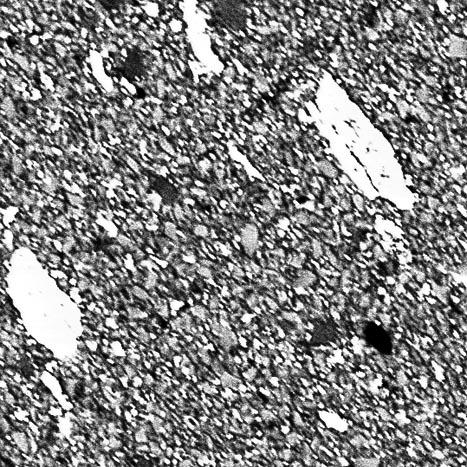

Characterization of ceramic particles in the micro and nanorange

Modern resin-based dental filling materials are composites composed of ceramic particles in the micro and nanorange. During clinical use wear particles are produced. The aim is to explore the biologic effects of such particles.